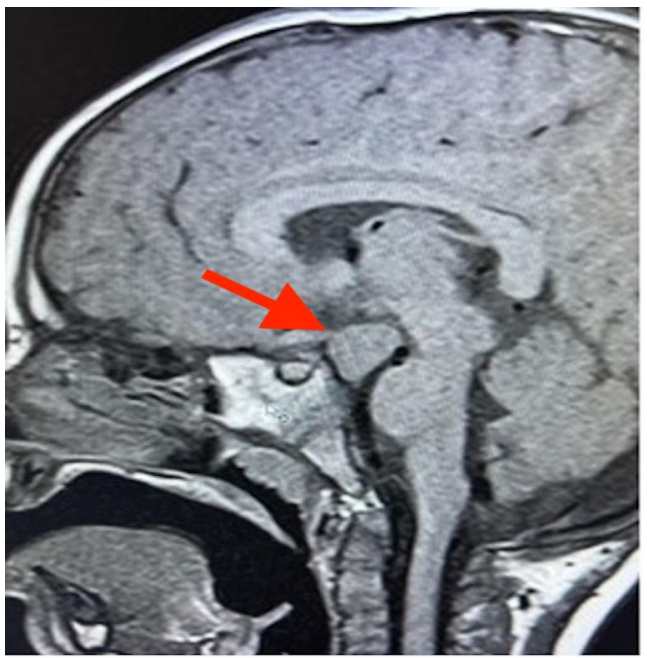

(normal range for 6 month to 4 years : 0,05- 0,50 pg/ml). Cranial magnetic resonance imaging focused in the sellar region showed an isointense expansive lesion relative to the gray matter behind the pituitary stalk and in relation to the floor of the third ventricle (Figure 3).

Figure 3. Cranial magnetic resonance imaging revealed an isointense expansive lesion behind the pituitary stalk (red arrow).

Puberty begins with the pulsatile secretion of GnRH, which activates the hypothalamic-pituitary-gonadal axis. Tanner stages are used to evaluate pubertal development. In boys, the onset of puberty is characterized by testicular enlargement, which corresponds to Tanner stage 2 of genital development, defined as a testicular volume greater than 4 ml7. In this case, the clinical examination revealed a testicular volume of 5 ml as an element of precocious puberty along with an increase of growth velocity for the patient’s age and sex. Hormonal evaluation showed elevated basal gonadotropins and testosterone. While the gold standard for evaluation is the measurement of gonadotropins after stimulation with GnRH, the measurement of basal luteinizing hormone is also a viable alternative.  An LH value ≥ 0.3 IU/l, as determined by immunochemiluminescence, can be considered an appropriate cut-off point for the diagnosis of central precocious puberty1. In the imaging evaluation, an isointense expansive lesion was identified in the gray matter behind the pituitary stalk, adjacent to the floor of the third ventricle, consistent with hypothalamic hamartoma9.